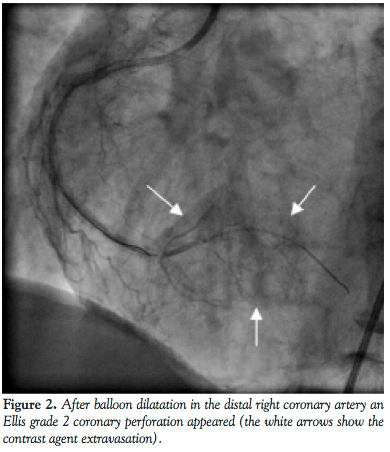

The coronary angiogram showed the left coronary system free of significant disease. However in the RCA a long total occlusion was seen in the Endeavor stents (Medtronic) implanted in the distal portion. Contrarily, in the proximally implanted Nobori stent, no restenosis was revealed. Furthermore, an intermediate de novo stenosis was also demonstrated in the mid RCA segment (Figure 1).

The RCA total occlusion was easily crossed with a hydrophilic PT Graphix Intermediate guidewire (Boston Scientific). With the use of a 2.5 mm x 20 mm Sprinter Legend (semicompliant) balloon (Medtronic), predilatation was performed in the distal segment at 19 atm. After restoration of the TIMI III flow in the whole vessel, an Ellis grade 2 perforation appeared in the posterior atrioventricular area (Figure 2). The exact site of the perforation was not evident because an overt contrast agent was not detected. Nevertheless it was

reasonable to assume that the perforation occurred near the distal stent edge as a consequence of the high-pressure predilatation. To seal the perforation, the above-mentioned net wrapped stent, a 2.5 mm x 15 mm MGuard was introduced in the territory of crux cordis. The stent was positioned to cover the distal edge of the previously implanted Endeavor stent and the perforated posterolateral branch as well, and then it was deployed at nominal pressure (Figure 3). The overlapping part of the stent was postdilated with the aid of the stent balloon at 17 atm. The implantation of the MGuard stent resulted in successful sealing of the perforation and the contrast agent extravasation was abolished. The original restenotic lesion and the de novo mid segment lesion were managed by deploying 2 Xience Prime LL 3 mm x 33 mm stents (Abbott Vascular) at 20 atm (Figures 4 and 5). No signs of hemodynamic instability appeared. After the intervention, echocardiogram revealed only 6-7 mm pericardial fluid localized at the left ventricular posterior wall. There were no significant ECG changes and the maximum CPK level was 260 U/L (upper limit of normal is 170 U/l). The patient remained stable during the following hospital stay. She was discharged on a daily dose of aspirin 300 mg and clopidogrel 150 mg. At 6-month follow-up neither angina pectoris, nor sign of coronary ischemia were revealed.